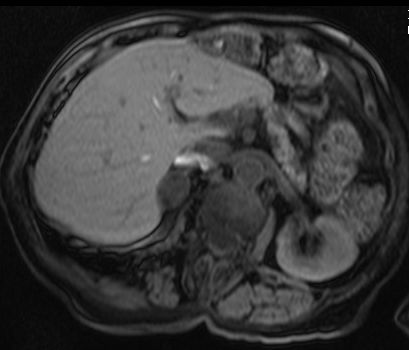

- 간: 드문 양성 종양으로, 간 비대 등의 증상을 유발할 수 있다.

간 腺瘤|선종중국어은 간의 드문 양성 종양으로, 간 비대 또는 기타 증상으로 나타날 수 있다.[1]3. 2. 내분비계